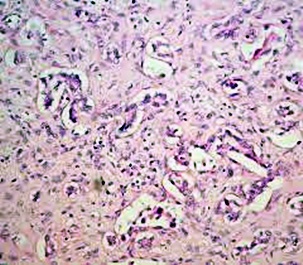

몸에 필요한 황색의 담즙색소 (빌리루빈)이 과도하게 쌓여 눈동자나 피부 등에 착색되는 현상을 말한다고 합니다. 이 담즙색소는 체내에 들어온 물질들이 분해되는 과정에서 생성되는 필요 없는 물질인데요. 일반적으로는 간에서 해독작용을 거친 후에 담즙으로 배설이 되는 것이 정상적이지만, 그렇지 못한 경우 황달이 발생하게 된다고 합니다.

황달이 생기는 이유는 담즙색소라고 알려진 빌리루빈이 과도하게 생기기 때문입니다. 빌리루빈은 우리 몸의 오래된 적혈구가 파괴되면서 생기는 물질인데요. 이 물질은 담즙에 녹아서 우리 몸의 배설물과 함께 배출이 되는 것이 정상적이지만 빌리루빈의 과잉생산이나, 간의 장애, 간세포나 담도의 손상에 의해 빌리루빈이 역류할 경우 발생된다고 합니다.